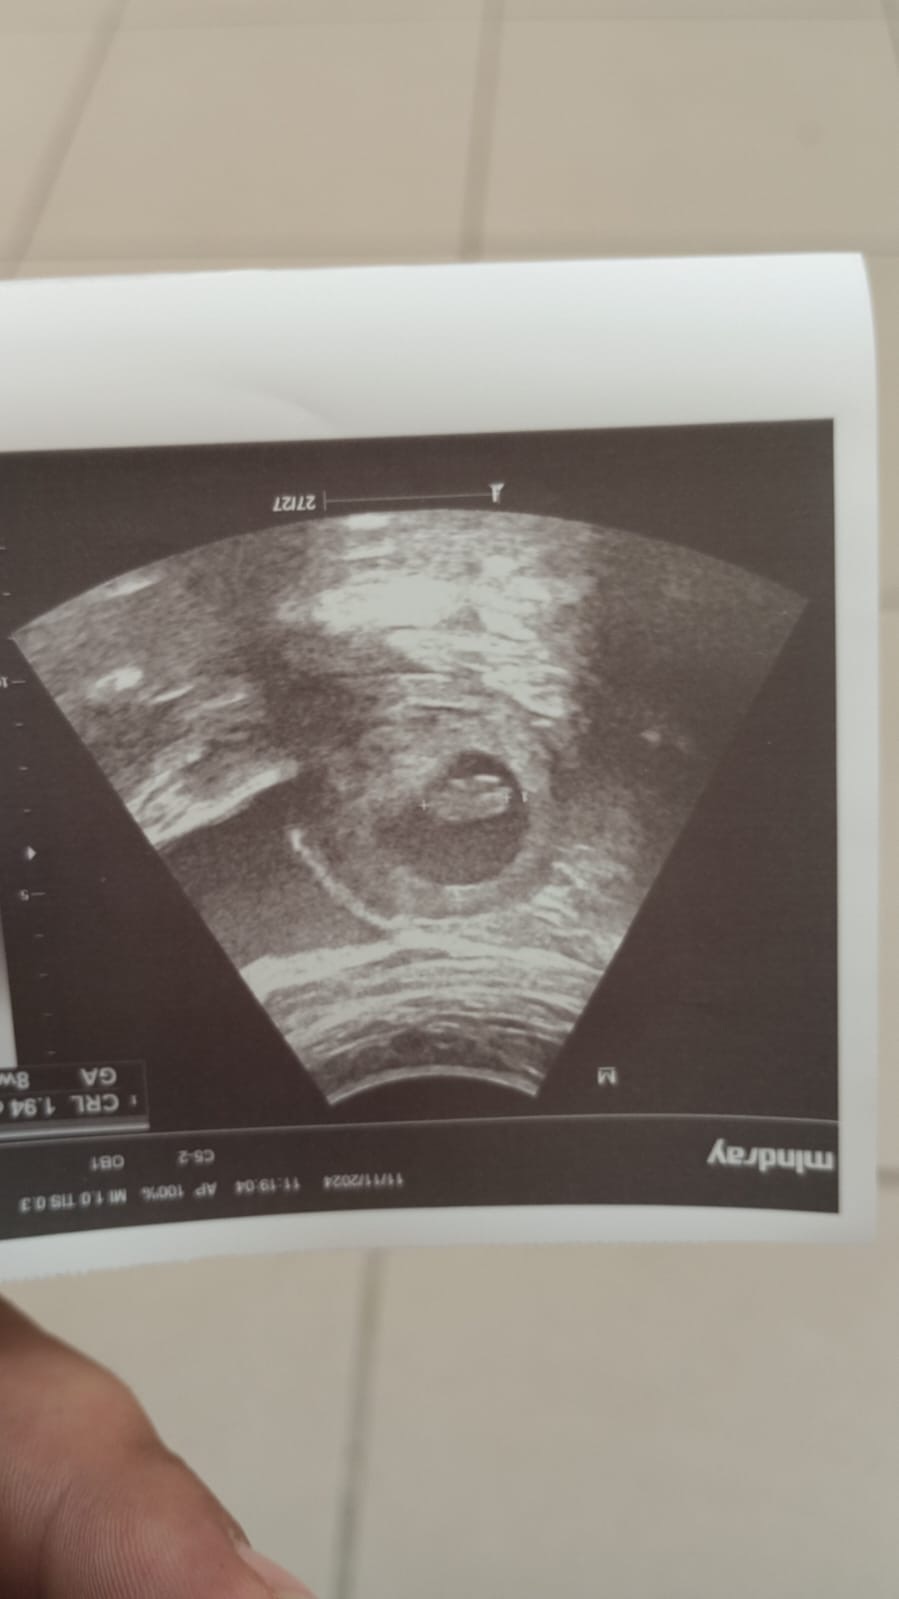

Benim daha orda 6 haftalık ilk ultroson resmi ama öteki ayın 15inde tekrar gidicem o zaman Bidaha atarım ![]()

Banada tahmin yapar mısınız